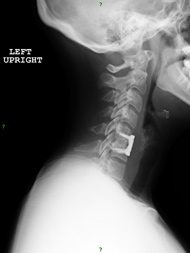

I had some diagnostic injections that helped point to the C4-5 level as the source of most of my pain. The injections gave me more than enough information to proceed with the C4-5 fusion. I also had a questionable pseudarthrosis (fracturing that won’t heal without intervention) at the C7-T1 level. Dr. Jatana recommended doing the C4-5 surgery first and waiting to see if the C7-T1 pseudarthrosis was still problematic after I recovered. There wasn’t a quick or easy solution for me and I really appreciated that Dr. Jatana conveyed to me that patience was part of my treatment plan.

Dr. Jatana operated on me in September 2013. The crushing pain on top of my shoulders and the nerve root pain that I was experiencing was better immediately after surgery. I’m able to work and exercise now. I am getting stronger every day and am able to do things that I haven't been able to do for years.